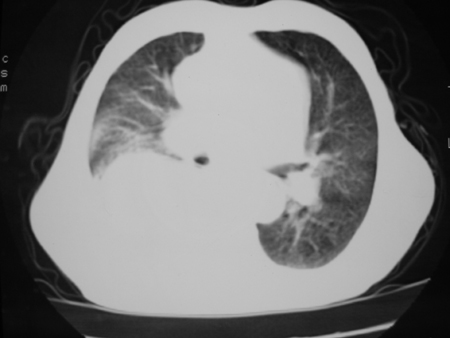

男77岁,胸痛就诊

右侧胸腔积液,部分包裹,右下肺膨胀不全,右下肺感染。

考虑右肺门占位并下叶不张 右胸包裹积液

右肺中叶及下叶炎症并胸腔积液(部分包裹),建议抽液后复查ct除外占位。

右侧胸腔积液,部分包裹,右下肺膨胀不全,右下肺感染